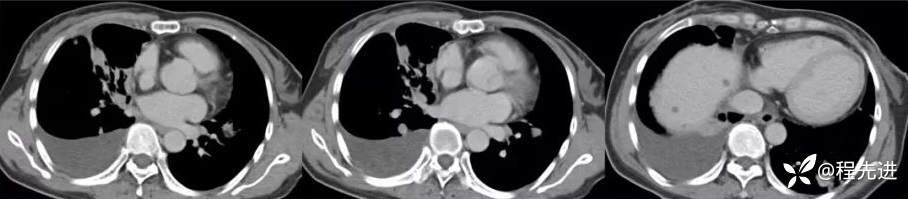

增强动脉期

增强静脉期